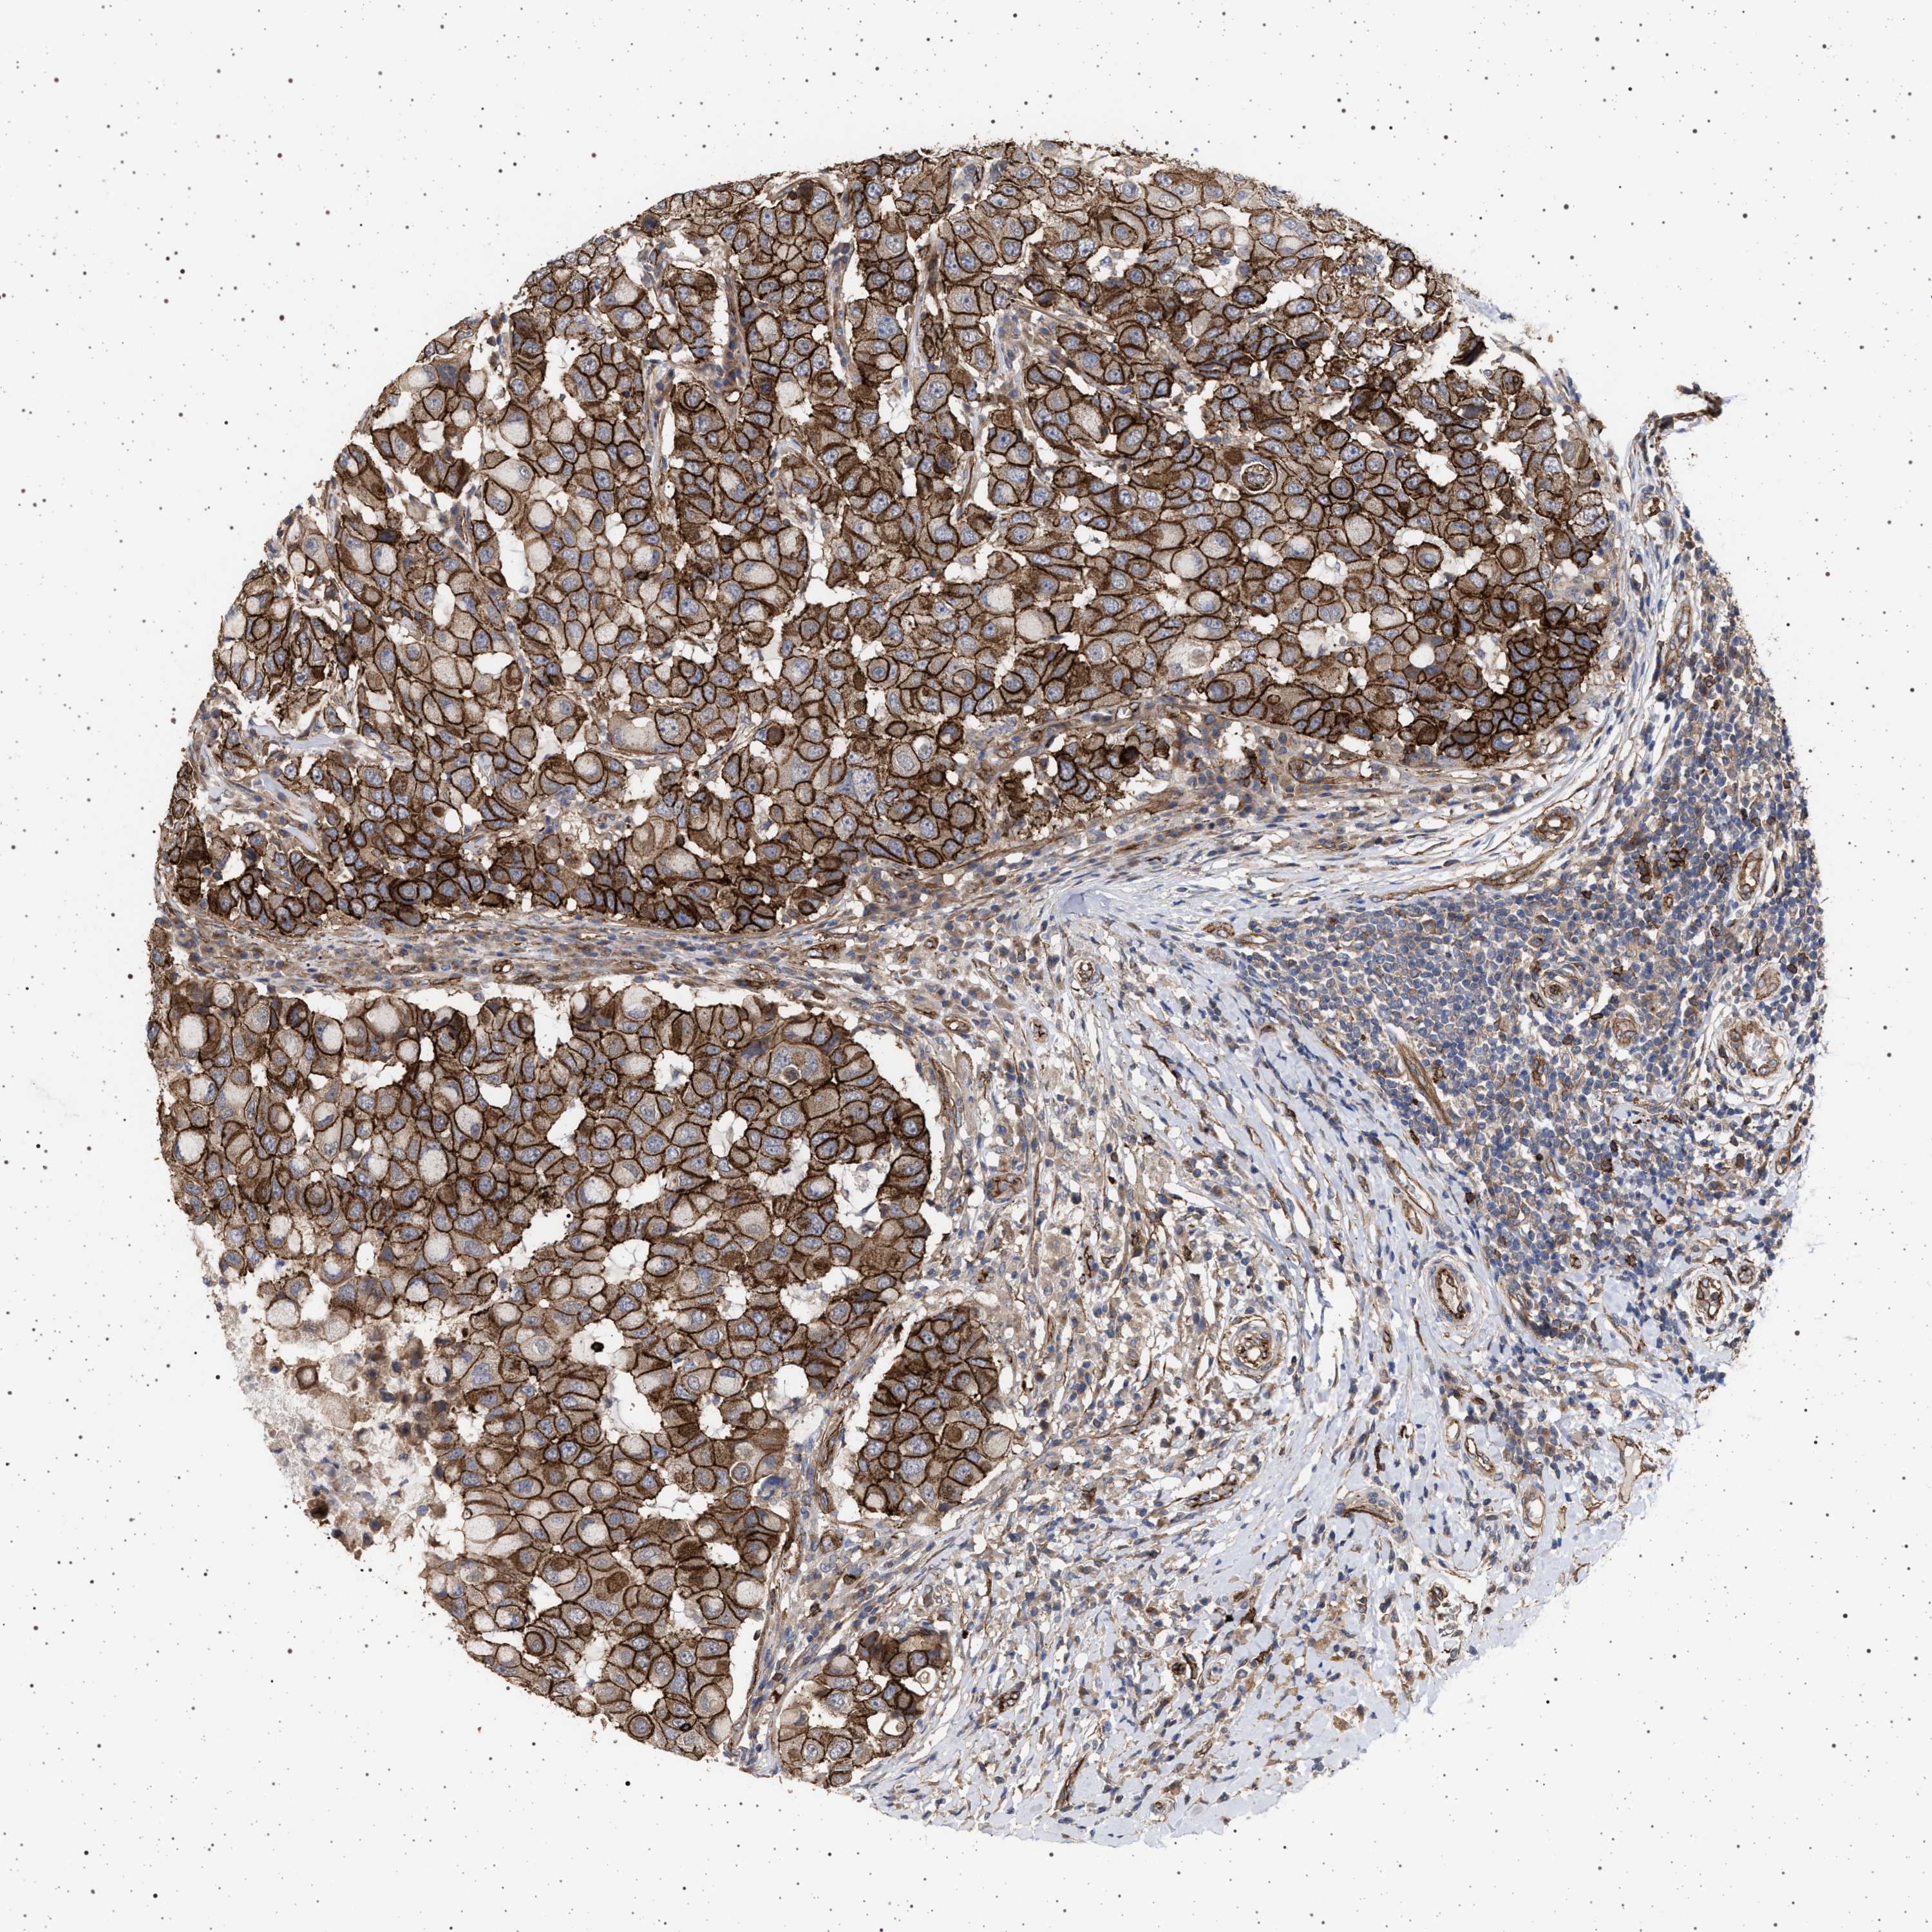

CANCER BREAST CANCER Show tissue menu

BRCA TCGA BRCA VALIDATION PROTEIN EXPRESSION

Breast cancer

Human cancer